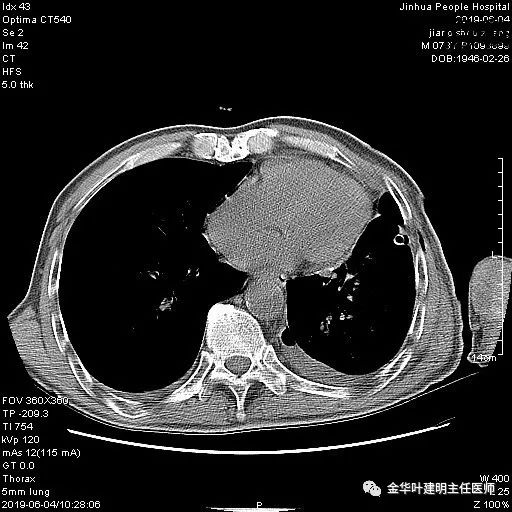

考虑左侧大量胸腔积液,遂进一步胸部CT检查:

以上是肺窗表现,下面为纵隔窗影像: